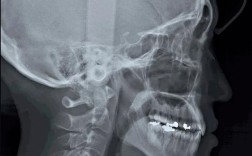

“牙齿矫正头颅侧位”指的是头颅侧位定位片,这是正畸诊断中极其重要的一种X光影像检查,它从侧面拍摄患者的头颅和面部,提供了骨骼、牙齿、软组织(如嘴唇)之间精确的空间位置关系信息。

它就像是正畸医生的“蓝图”或“导航地图”,帮助他们全面了解患者的面部结构,从而制定出最合适的矫正方案。

- 提供三维信息: 它能同时显示骨骼、牙齿、软组织的前后、垂直、深度三个维度的关系,这是口内照片、模型或全景片无法完全替代的。

- 揭示隐藏问题: 很多骨骼问题和牙齿的深部位置问题仅凭口腔检查难以发现,头颅侧位片能清晰揭示。

“牙齿矫正头颅侧位”是正畸诊疗中不可或缺的关键检查,它像一份详尽的“面部结构说明书”,让正畸医生能够深入了解患者的骨骼框架、牙齿排列和软组织轮廓,从而做出精准的诊断,制定科学、个性化、可预测的矫正方案,并最终实现功能与美观的双重改善,如果你正在考虑或正在进行牙齿矫正,医生要求拍摄这个片子,是非常必要和重要的步骤。